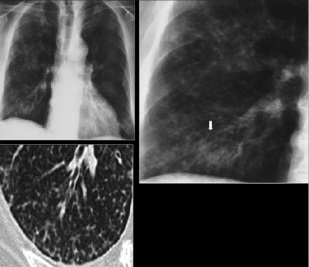

Tuberculosis creates cavities visible in x-rays like this one in the patient's right upper lobe.

In active pulmonary TB, infiltrates or consolidations and/or cavities are often seen in the upper lungs with or without mediastinal or hilar lymphadenopathy.[1] However, lesions may appear anywhere in the lungs. In HIV and other immunosuppressed persons, any abnormality may indicate TB or the chest X-ray may even appear entirely normal.[1]

2. Any cavitary lesion - Lucency (darkened area) within the lung parenchyma, with or without irregular margins that might be surrounded by an area of airspace consolidation or infiltrates, or by nodular or fibrotic (reticular) densities, or both. The walls surrounding the lucent area can be thick or thin. Calcification can exist around a cavity.